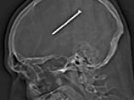

Как сообщает Sky News, рентген, сделанный в одной из больниц Чикаго показал, что Данте не просто оцарапал себя пневматическим пистолетом для гвоздей, а вогнал себе в голову трехдюймовый гвоздь. Правда, настолько удачно, что не повредил ни один из важных нервных центров: он мог двигаться, говорить, сохранил память. А учитывая, что в самом мозге болевых рецепторов нет, никаких физических неудобств гвоздь Аутулло не доставил.

Фото рентгеновского снимка Аутулло запостил на Facebook прямо из машины скорой помощи, которая доставляла его из одной больницы в другую для проведения операции.